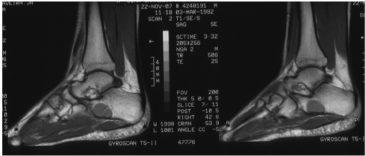

A decision is made to conduct magnetic resonance imaging (MRI) of the foot to identify the specific type of injury. The presence of a well-defined lytic lesion is confirmed, approximately 30x22x20 mm in the anteroinferior part of the calcaneus, with hypointense sequences enhanced on T1, which includes hyperintense sequences with fat suppression.

Findings are compatible with the diagnosis of a simple bone cyst (Figure 1).

Figure 1. Lytic lesion in calcaneus. Detail of the lateral X-ray of the foot

It was also decided to perform a magnetic resonance imaging (MRI) of the foot to try to identify the type of injury. The presence of a well-defined lytic lesion was confirmed, approximately 30x22x20 mm in the antero-inferior part of the calcaneus, hypo intense in the sequences enhanced in T1 and hyper intense in the sequences with fat suppression. Findings compatible with the diagnosis of simple bone cyst (Figure 2A,2B).

Figure 2A. In T1-weighted sequences, the lesion is well defined and clearly hypointense

Figure 2B. STIR in which the hyperintensity of the lesion in the calcaneus is appreciated